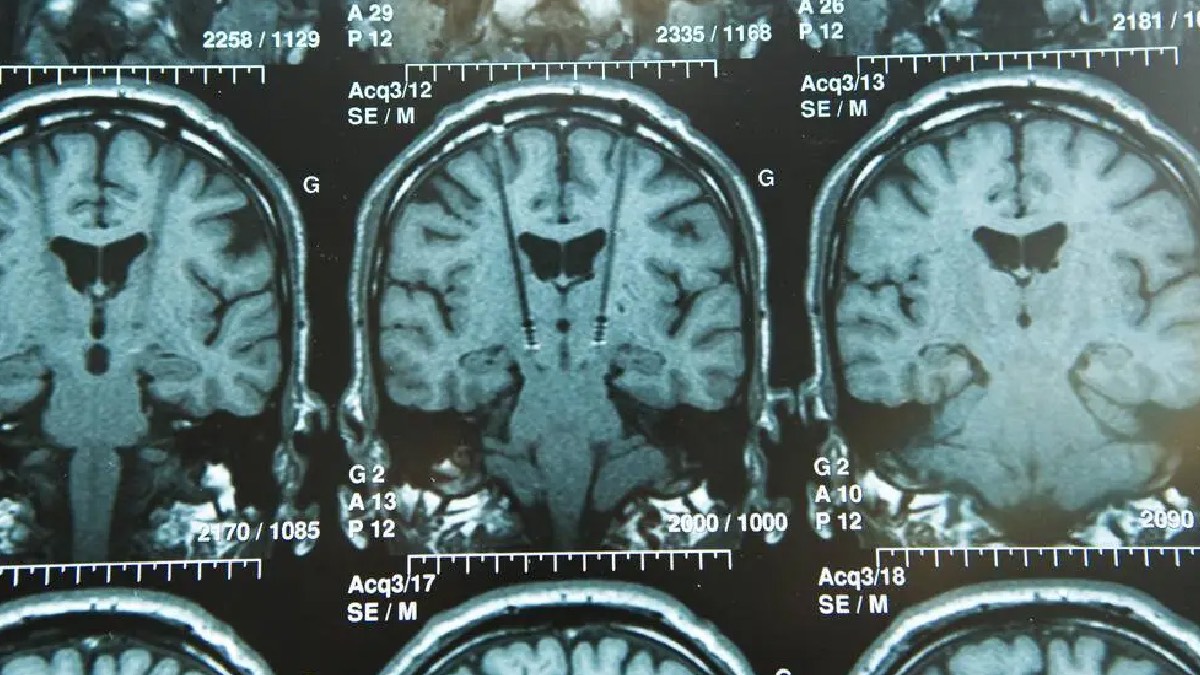

Un ACV ocurre cuando se interrumpe el suministro de sangre de una parte del cerebro. Un accidente cerebrovascular isquémico, el tipo más común, es causado por una arteria bloqueada en el cerebro. Con los accidentes cerebrovasculares hemorrágicos, un vaso sanguíneo en el cerebro se escapa o estalla y causa sangrado en el cerebro. El bloqueo del flujo sanguíneo conduce a la muerte celular, y cuanto más dura el bloqueo, más células cerebrales se lesionan. Cuando se produce una hemorragia en el cerebro, las células se lesionan debido al aumento de la presión dentro del cerebro y debido a lesiones directas de la sangre, lo que las lleva, posteriormente, a la degradación.

La mayoría de las cirugías se realizan pocas horas después del accidente cerebrovascular, cuando el paciente se encuentra en la fase aguda, explica el Dr. Fox. La cirugía en pacientes con accidentes cerebrovasculares isquémicos se centra en restaurar el flujo sanguíneo al cerebro. La cirugía en pacientes con accidente cerebrovascular hemorrágico se centra en tratar la causa del sangrado y aliviar la presión sobre el cerebro.